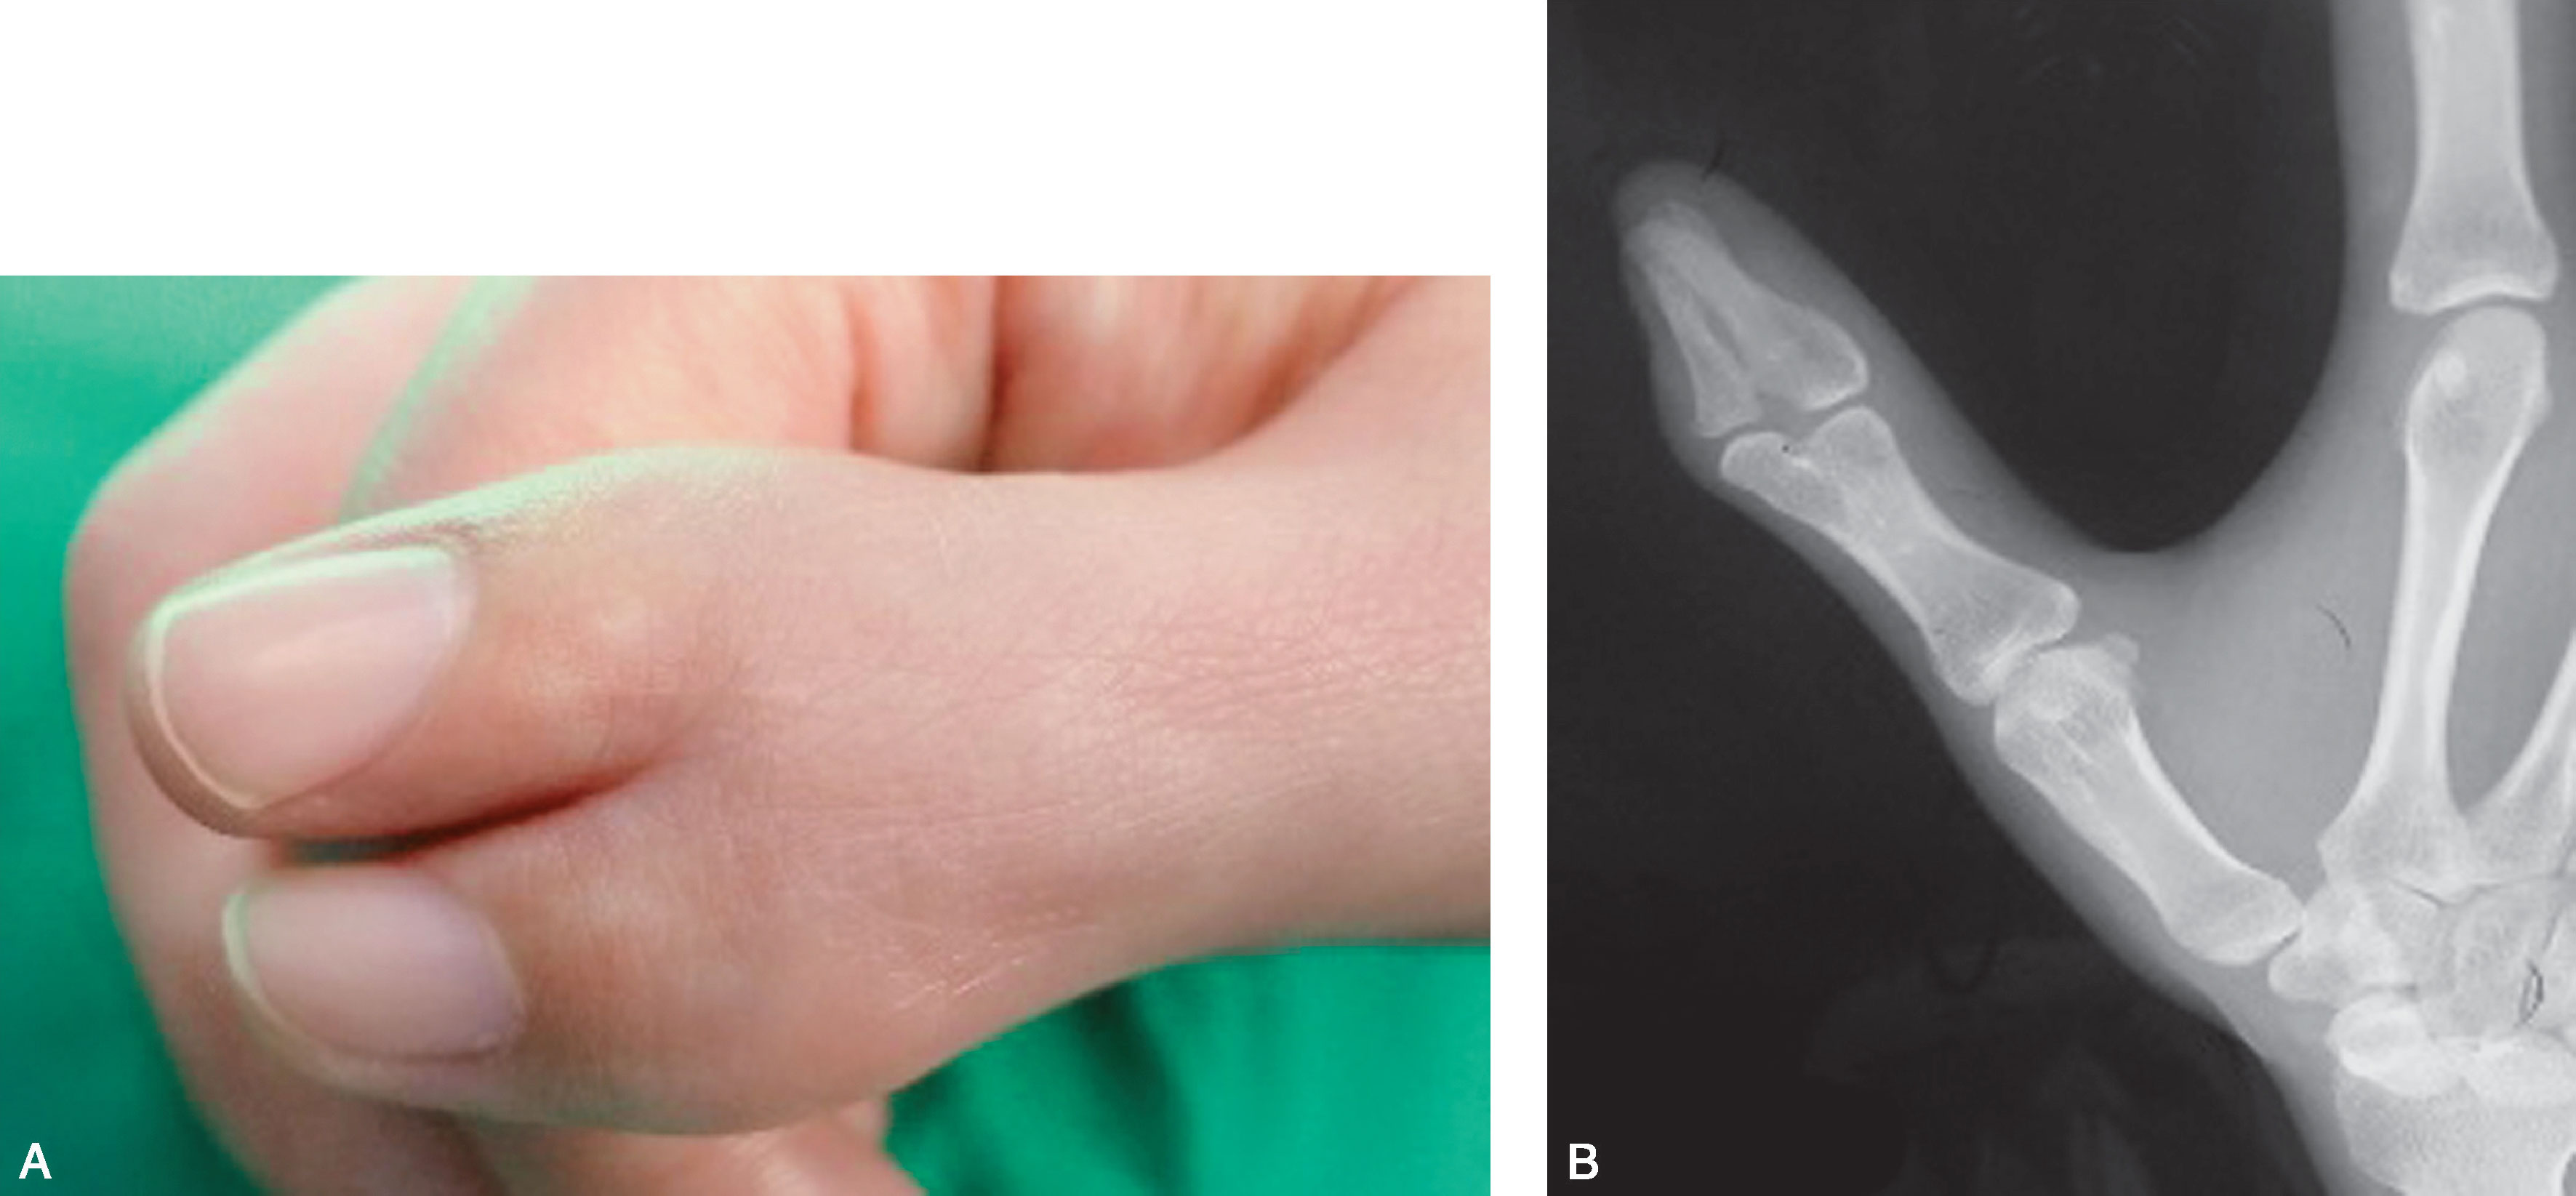

1.Ⅰ型 末节指骨未完全分裂,近节指骨正常或不正常,共用一个骨骺,并与近节指骨远端形成关节(图2-1-1~图2-1-4)。

图2-1-2 Ⅰ型病例2

A.主、次拇指外形差异较小,各自的指甲外形尚好且大小基本接近,融合在一起,可以选择切除任何一侧拇指,同时重建甲沟,或行主、次拇指融合;B.X 线片显示主次拇指远节指骨近端融合,远端分叉,分叉部分指骨大小差距较大,从X 线片结果看,可以切除桡侧拇指,也可行主、次拇指融合